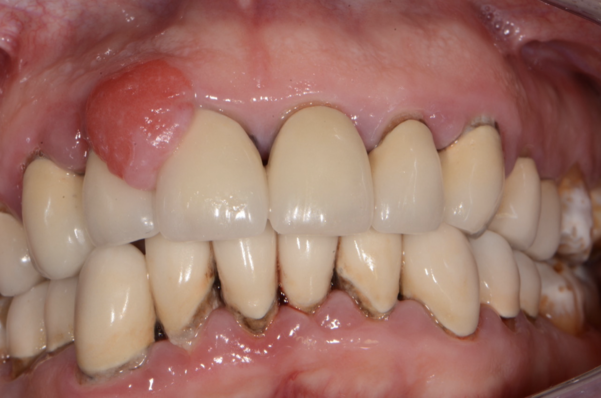

Epulide protesi fissa

BlogGengive

Come si risolve il problema dell’epulide?